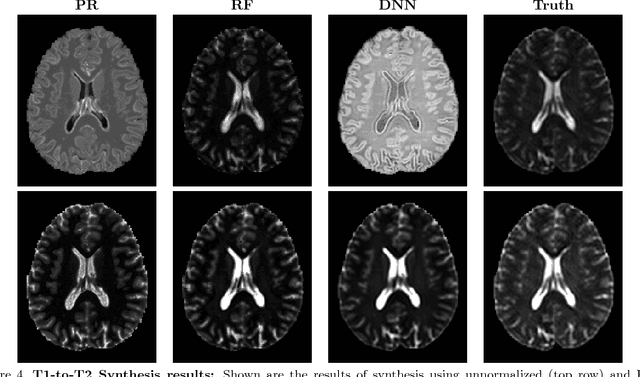

Abstract:Image synthesis learns a transformation from the intensity features of an input image to yield a different tissue contrast of the output image. This process has been shown to have application in many medical image analysis tasks including imputation, registration, and segmentation. To carry out synthesis, the intensities of the input images are typically scaled--i.e., normalized--both in training to learn the transformation and in testing when applying the transformation, but it is not presently known what type of input scaling is optimal. In this paper, we consider seven different intensity normalization algorithms and three different synthesis methods to evaluate the impact of normalization. Our experiments demonstrate that intensity normalization as a preprocessing step improves the synthesis results across all investigated synthesis algorithms. Furthermore, we show evidence that suggests intensity normalization is vital for successful deep learning-based MR image synthesis.